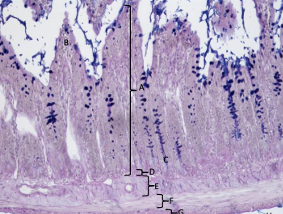

warstwa drobinowa

warstwa zwojowa z komórkami Purkiniego

warstwa ziarnista

to wszystko tworzy istotę szarą

istota biała

móżdżek nr 421